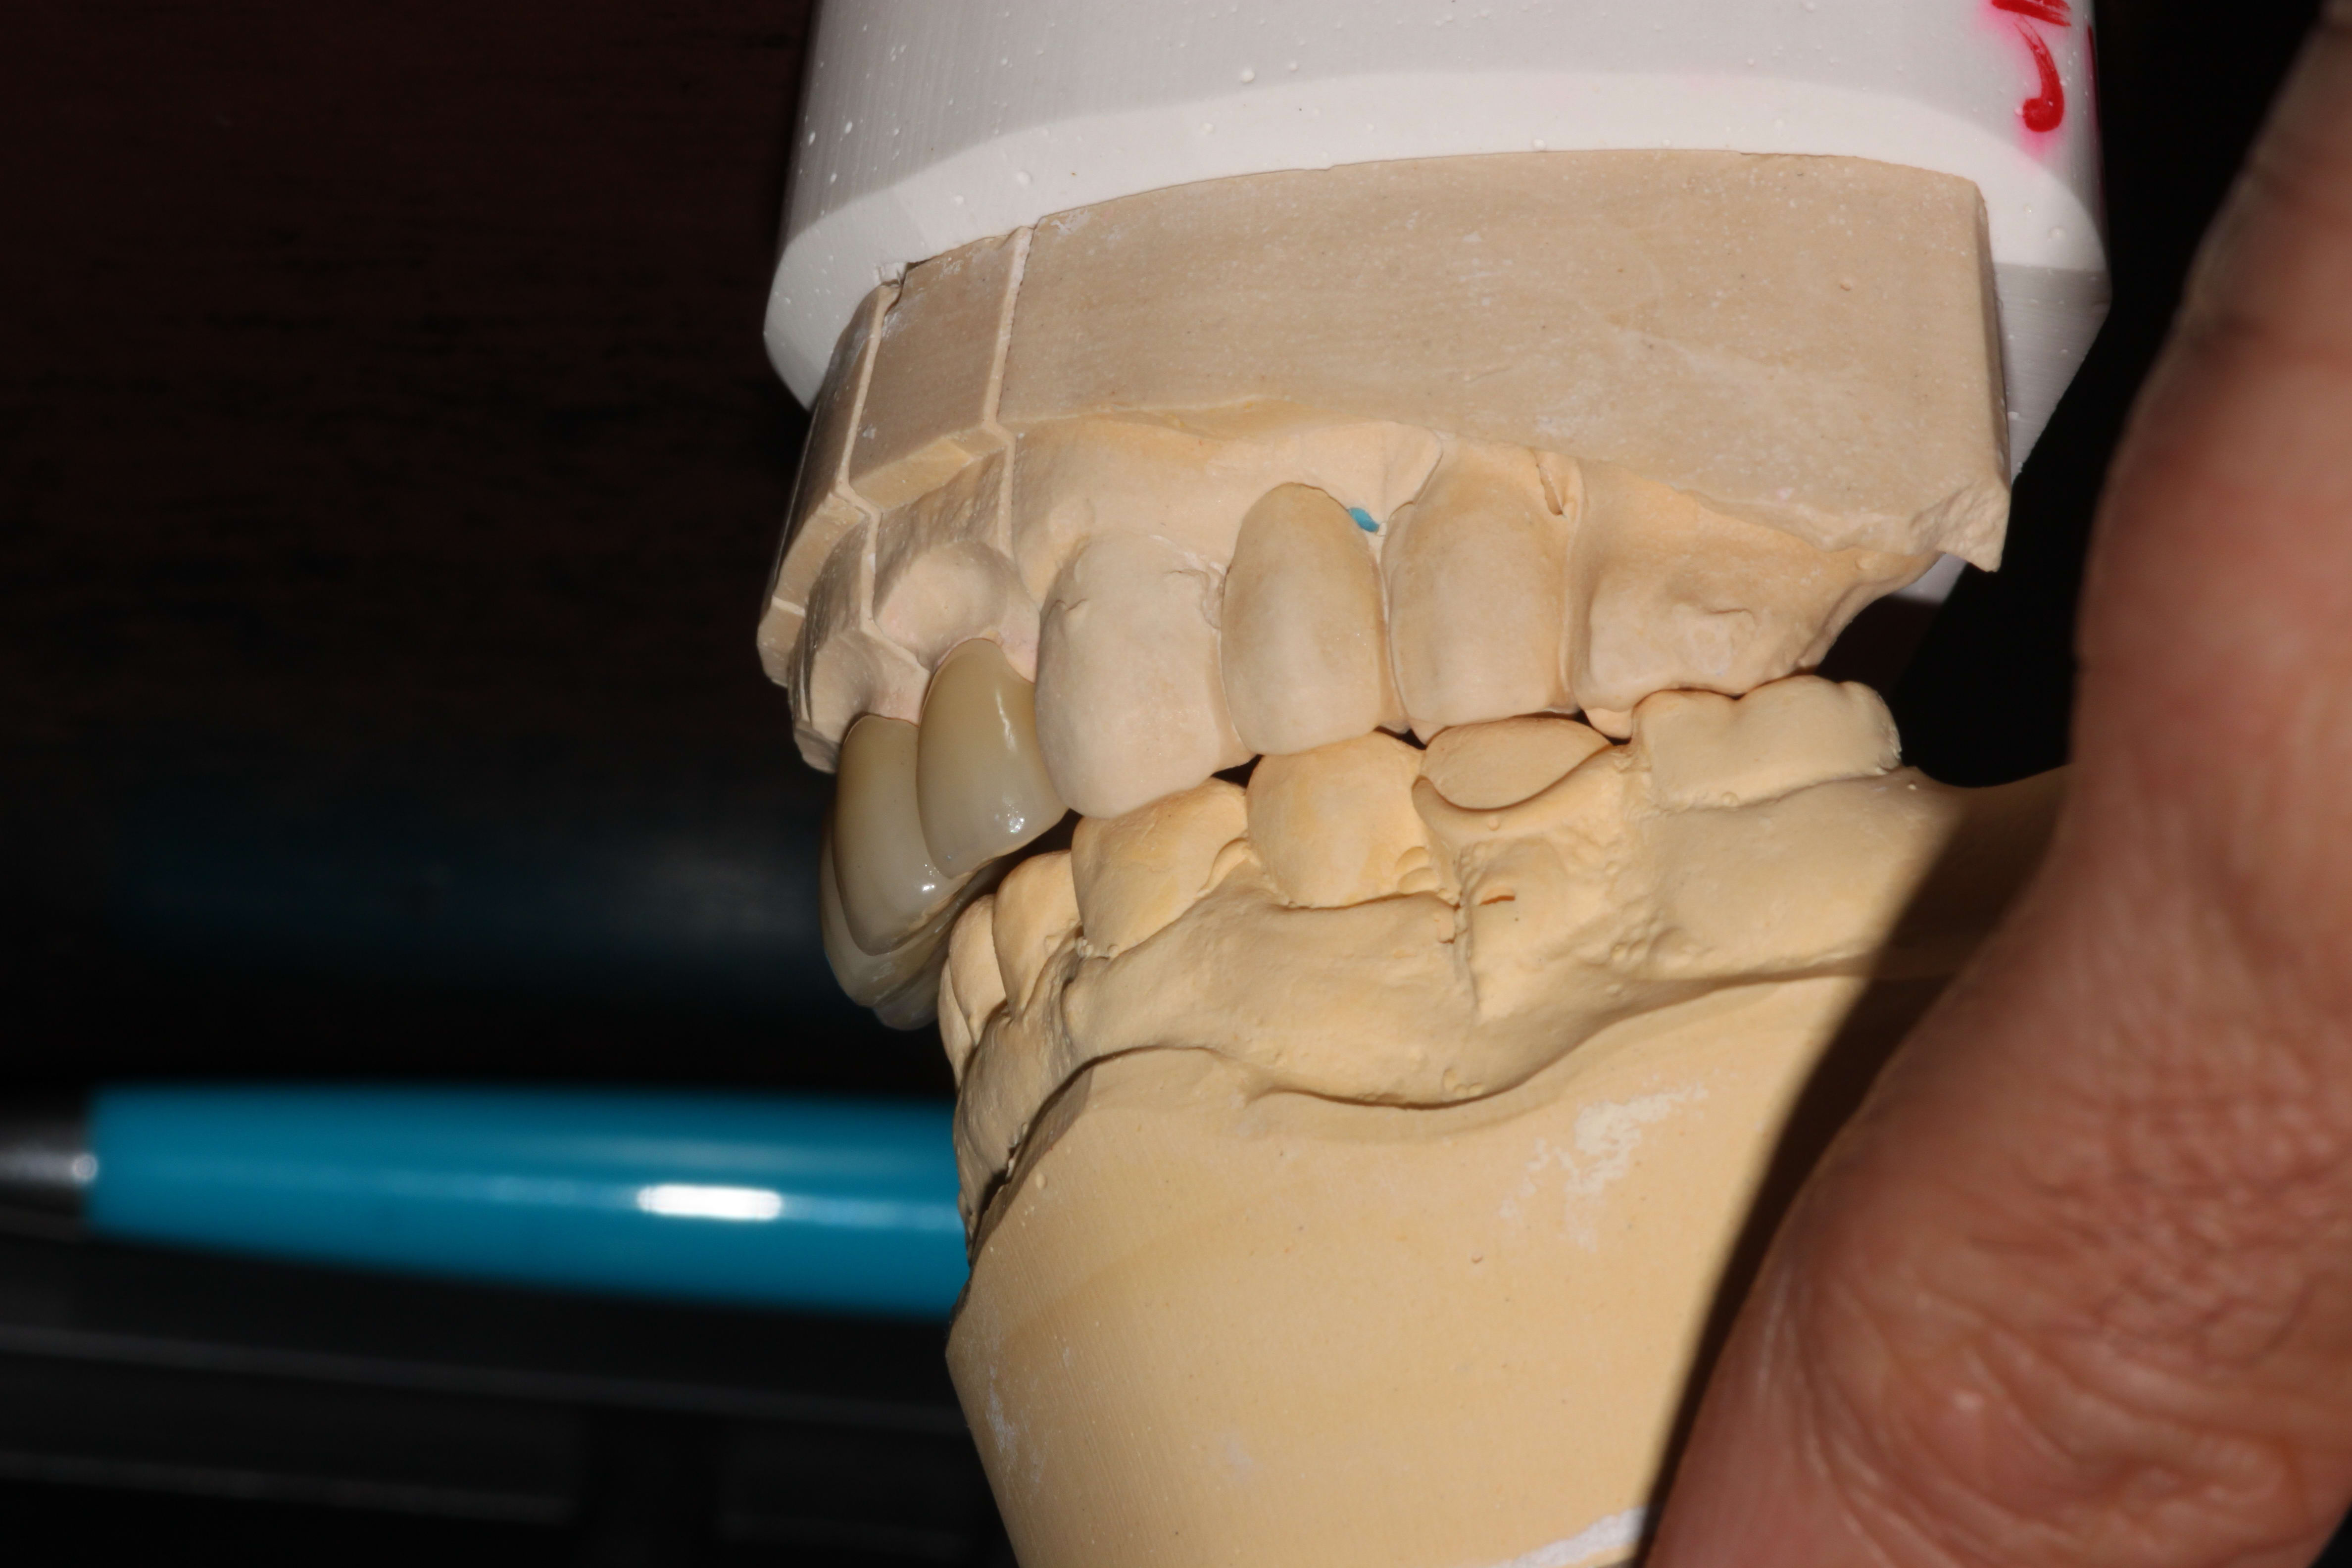

13/06/2018 à 13h30

Et enfin, les antérieures sur zircone.

Pour guider le prothésiste, j'ai tout simplement fini de travailler les anatomies sur le plâtre des provisoires, sans m'embêter à peaufiner en bouche.

Img 4384 fzco4a - Eugenol

Img 4385 zsazaz - Eugenol

Img 4386 tagv5e - Eugenol